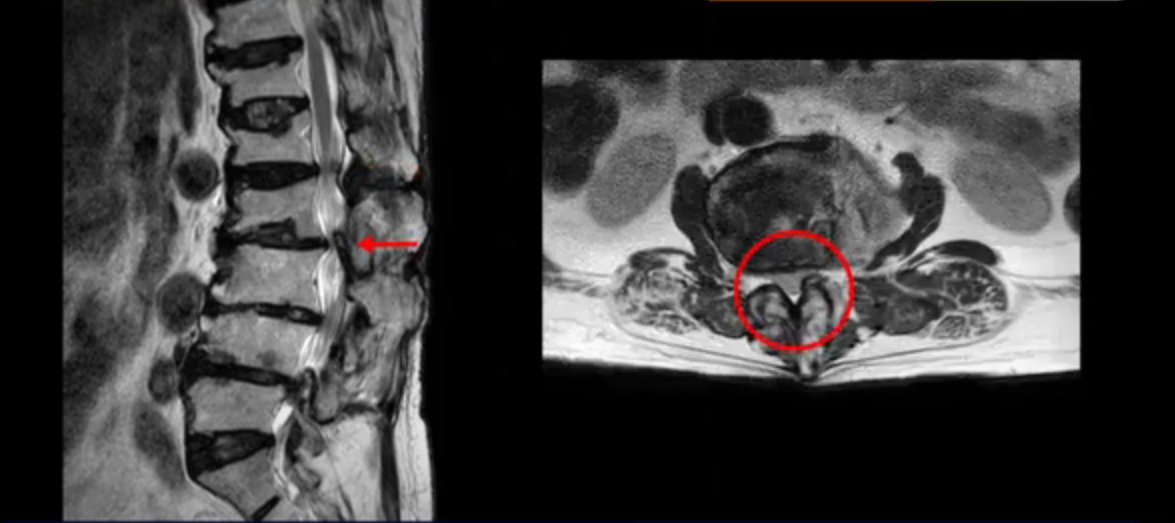

이 환자분은 허리 여러 마디가 다 안 좋아서 오랫동안 허리가 아프셨고 허리도 일찌감치 굽으셨습니다. MRI를 보시면 허리 여러 마디가 심하게 안 좋습니다.

보시다시피 4번 5번 마디에는 심한 중심성 협착이 있고

1번 2번,

2번 3번,

3번 4번에도 중심성 협착이 있습니다.

또 신경 가지가 빠져나가는 추간공도 좁아져 있습니다. 이런 이유로 환자분의 다리가 저리고 아픈 겁니다.

또한 척추뼈 여러 개가 압박 골절과 변형으로 찌그러져 있고

골다공증도 심하시고 보시다시피 근육량이 너무 적습니다. 근육이 정상적인 분들과 비교해보면 근육이 얼마나 적은지 알 수 있습니다.